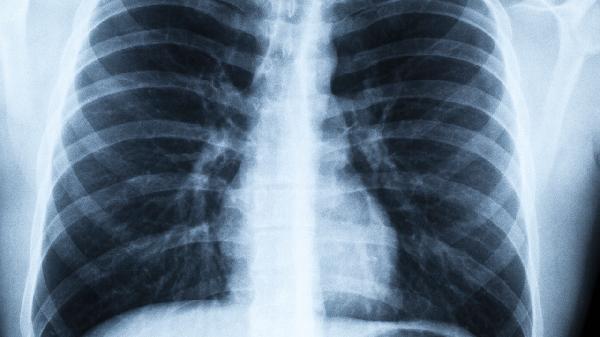

• 病毒性肺炎怎么快速治好

病毒性肺炎的治疗通常包括抗病毒药物、对症处理、调节免疫、预防并发症以及中医辅助等综合手段,有助于加快康复进程。这种疾病多...

• 病毒性肺炎和感冒有哪些症状区别

病毒性肺炎在初期可能表现为发热、干咳和乏力,这些症状与普通感冒相似,但随着病情发展,会逐渐出现呼吸急促、胸痛等更明显的特...